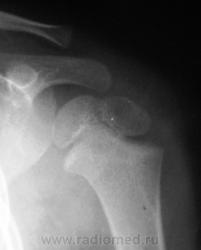

Для сравнения, дежурный хирург, попросил сделать правый плечевой сустав.

Перелом левой ключицы